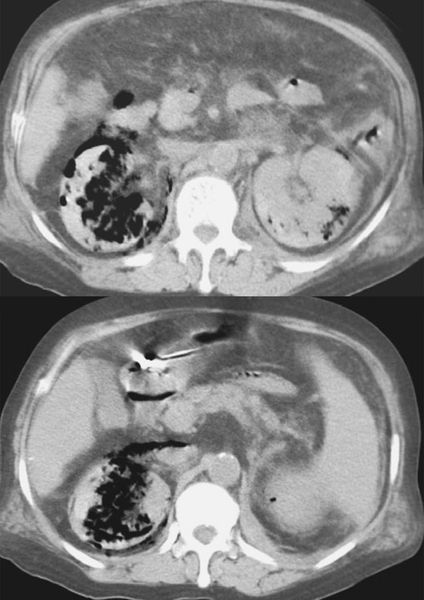

Характерной чертой эмфизематозного пиелита является скопление газа в тканях лоханки и чашечках. В большинстве случаев возбудителем заболевания выступает кишечная палочка. Хотя учёные ещё не до конца поняли, как в этом случае формируется газ, принято считать, что бактерия вызывает кислотную ферментацию глюкозы, в процессе которой образуются углекислый газ, водород, азот и др. [4][22][23] Чаще всего эмфизематозный пиелит диагностируют у ослабленных пациентов с длительным неконтролируемым или декомпенсированным сахарным диабетом, осложнённым патологией почек и нарушением оттока мочи.

В зависимости от распространённости газа, выделяют 5 типов болезни:

- I класс — газ находится исключительно в чашечно-лоханочной системе (непосредственно эмфизематозный пиелит);

- II класс — газ проникает в паренхиму почки;

- IIIА класс — газ распространился на ткани, окружающие почку;

- IIIВ класс — газ выходит за пределы тканей, окружающей почку, т. е. проникает в мышцы или подкожную клетчатку;

- IV класс — патологический процесс распространяется на обе почки или поражает единственную почку (т. е. вторая отсутствует) [3].

Скопление газа в паренхиме почки [24]